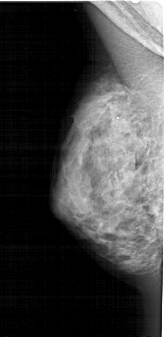

A_1660_1.LEFT_MLO

LEFT_MLO LINES 5041 PIXELS_PER_LINE 2476 BITS_PER_PIXEL 12 RESOLUTION 43.5 NON_OVERLAY

FILE: A_1660_1.RIGHT_MLO.OVERLAY

TOTAL_ABNORMALITIES 1

ABNORMALITY 1

LESION_TYPE CALCIFICATION TYPE PUNCTATE DISTRIBUTION SEGMENTAL

ASSESSMENT 4

SUBTLETY 1

PATHOLOGY BENIGN

TOTAL_OUTLINES 1

BOUNDARY